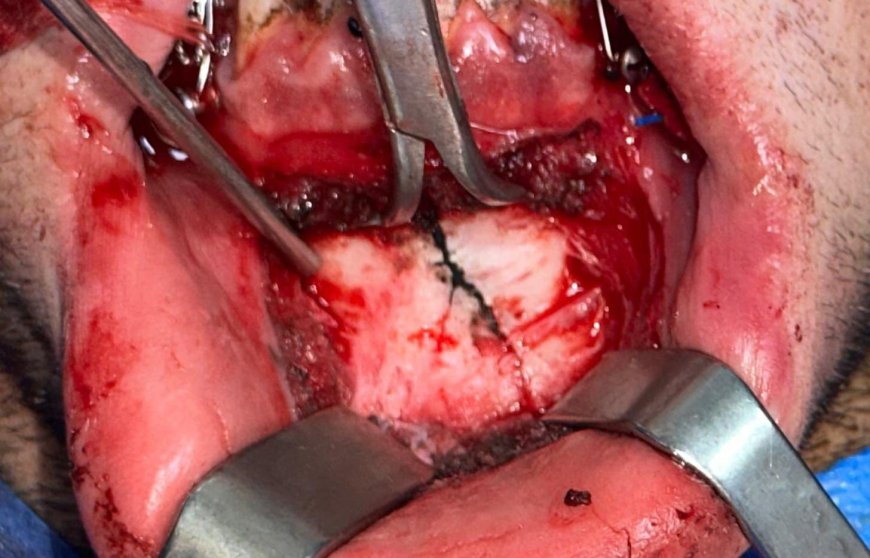

وفي هذا السياق، نجح الفريق الطبي بمستشفى عين شمس العام في إجراء جراحة دقيقة للوجه والفكين لإحدى الحالات المصابة إثر حادث سير، تم تثبيت كسر الفك السفلي تحت تأثير التخدير الكلي، في تدخل جراحي دقيق أسهم في استقرار الحالة وتحسين فرص التعافي.